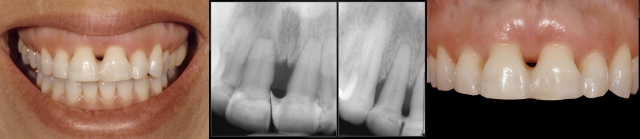

Mobile teeth: Yes

Splinting teeth with mobility due to short roots resulting from a history of periodontal disease, short roots caused by root resorption, or excessively tapered roots can be beneficial. This is especially true if they can be splinted to a tooth (teeth) that is not mobile, as it will help create stability. Even splinting multiple mobile teeth together can help create stability, especially if the teeth that are splinted turn the corner of the arch. The reason splinting can be helpful is that all teeth are mobile in the same direction (buccal-lingual); however, depending on where the teeth are positioned in the arch, their buccal-lingual direction may vary in different vectors.